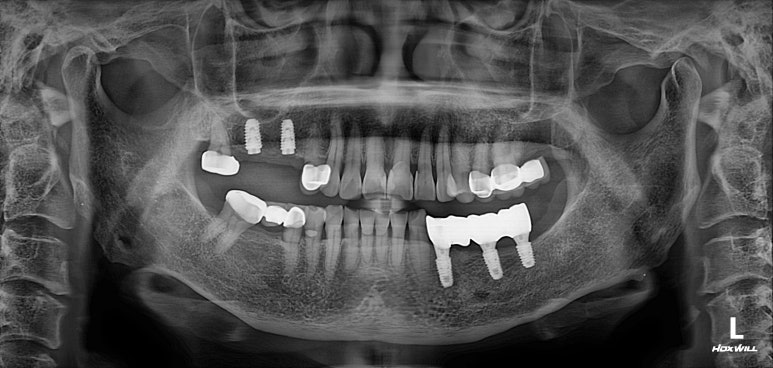

저희 병원에 작년에 오셨던 여자환자분입니다.

왼쪽 아래 어금니가 2개가 없으신 것을 아실 수 있으실텐데,

그 자리에 편측 틀니를 쓰고 계셨고, 너무너무 불편하여 임플란트로 치료 받으러 내원하셨습니다.

왼쪽 아래 큰어금니 두개가 없었고,

교합면 사진을 보시면, 앞의 두 치아에 surveyed crown (서베이드 크라운)을 설치하고 부분 틀니를 사용하게 하심을 단번에 알 수 있었습니다.

중요한 것은 해당 부위의 대구치 두 개를 뽑은지가 너무 오래되셨고, 틀니를 사용하셔서

대부분의 부착치은 (각화치은)이 사라져 있는 상태였습니다.

약 6주 후 왼쪽 아래 어금니 부위에 뼈이식을 동반하여

임플란트 1차 수술을 시행하였습니다.

왼쪽 아래 네 개의 어금니를 만들어 드려야 했기에, 과반수가 넘는 3개의 임플란트 수술을 계획하였습니다.

#34,36,37 자리에 임플란트를 식립할 예정이었어요.

#34번 부위는 임플란트를 위치시키고 나면 협측으로 뼈이식을 반드시 넉넉하게 해야할 모양새였습니다.

비교적 뽑은지 오래되었던 #36,37 치아는 잇몸뼈가 넉넉하게 보였습니다.

두 큰어금니 부위는 하치조신경관(아래이틀신경)만 조심해서 적절한 임플란트를 심어놓으면 되었습니다.

임플란트 1차수술

이렇게 예쁘게 3개의 임플란트를 심어드렸습니다.

마무리는 갈끔한 엑스레이 사진으로 !!!